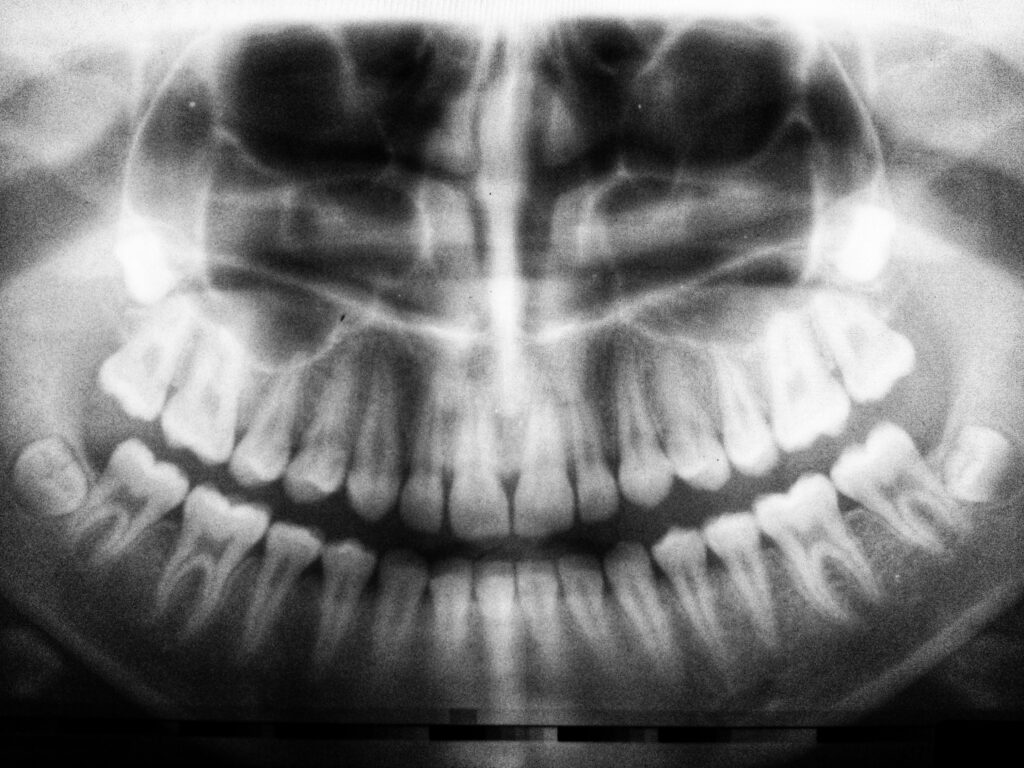

Dental X-rays, also known as radiographs, are images that allow your dentist to see what’s happening beneath the surface of your teeth and gums. This technology helps identify hidden issues like cavities, infections, impacted teeth, bone loss, and even tumors.

Even though dental X-rays involve some radiation, they are incredibly valuable tools that help:

Detect early signs of cavities, even those that are hidden between teeth

Monitor gums and bone health, which can help detect gum disease or bone loss

Plan for procedures like root canals, implants, or extractions

Spot early warning signs of oral cancer, tumors, or cysts